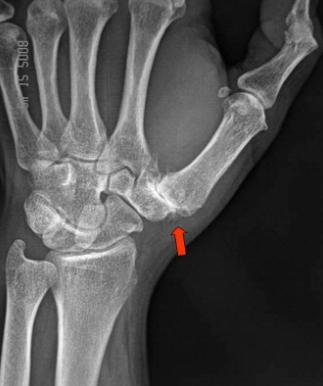

The

Triquetral bone was displaced, having rotated on its vertical axis

( see left diagram ). Its lateral edge was prominent and although

there was some mobility between it and its neighbours, it remained

in a relatively depressed position. This gave rise to mild inflammation

in the joint and the tendons which pass over it on the palmar side.

The result for 'bowing' was profound difficulty.